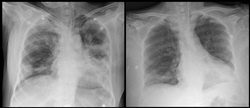

또 다른 완치자 이모 씨(67·여자)는 코로나19 진단 3일째 호흡 곤란으로 산소요구량이 높아지고, 왼쪽 폐의 상태가 악화되면서 세브란스병원으로 이송됐다.

이송 당시 호흡 속도는 분당 24회, 산소포화도는 93%(일반 평균 95% 이상)이었다. 면역결핍(림프구감소증)과 함께 CRP 역시 314mg/L까지 상승했고, 인공호흡기를 부착하기에 이르렀다. 말리리아치료제·에이즈치료제 투입, 산소 수치를 높이기 위해 몸을 뒤집는 치료를 시도했으나 림프구감소증과 고열은 지속됐다.

이 씨의 경우에도 완치자의 회복기 혈장을 12시간 간격으로 2회 투여했다. 혈장 투여와 스테로이드 시쵸를 시행한 후 림프구 수가 회복되고, 바이러스 농도도 감소했다. 흉부 X-ray 검사에서 폐의 침윤이 몰라보게 좋아졌고, CRP 역시 정상 수준을 회복했다. 이 씨는 완치 판정을 받고 지난달 말게 퇴원했다.